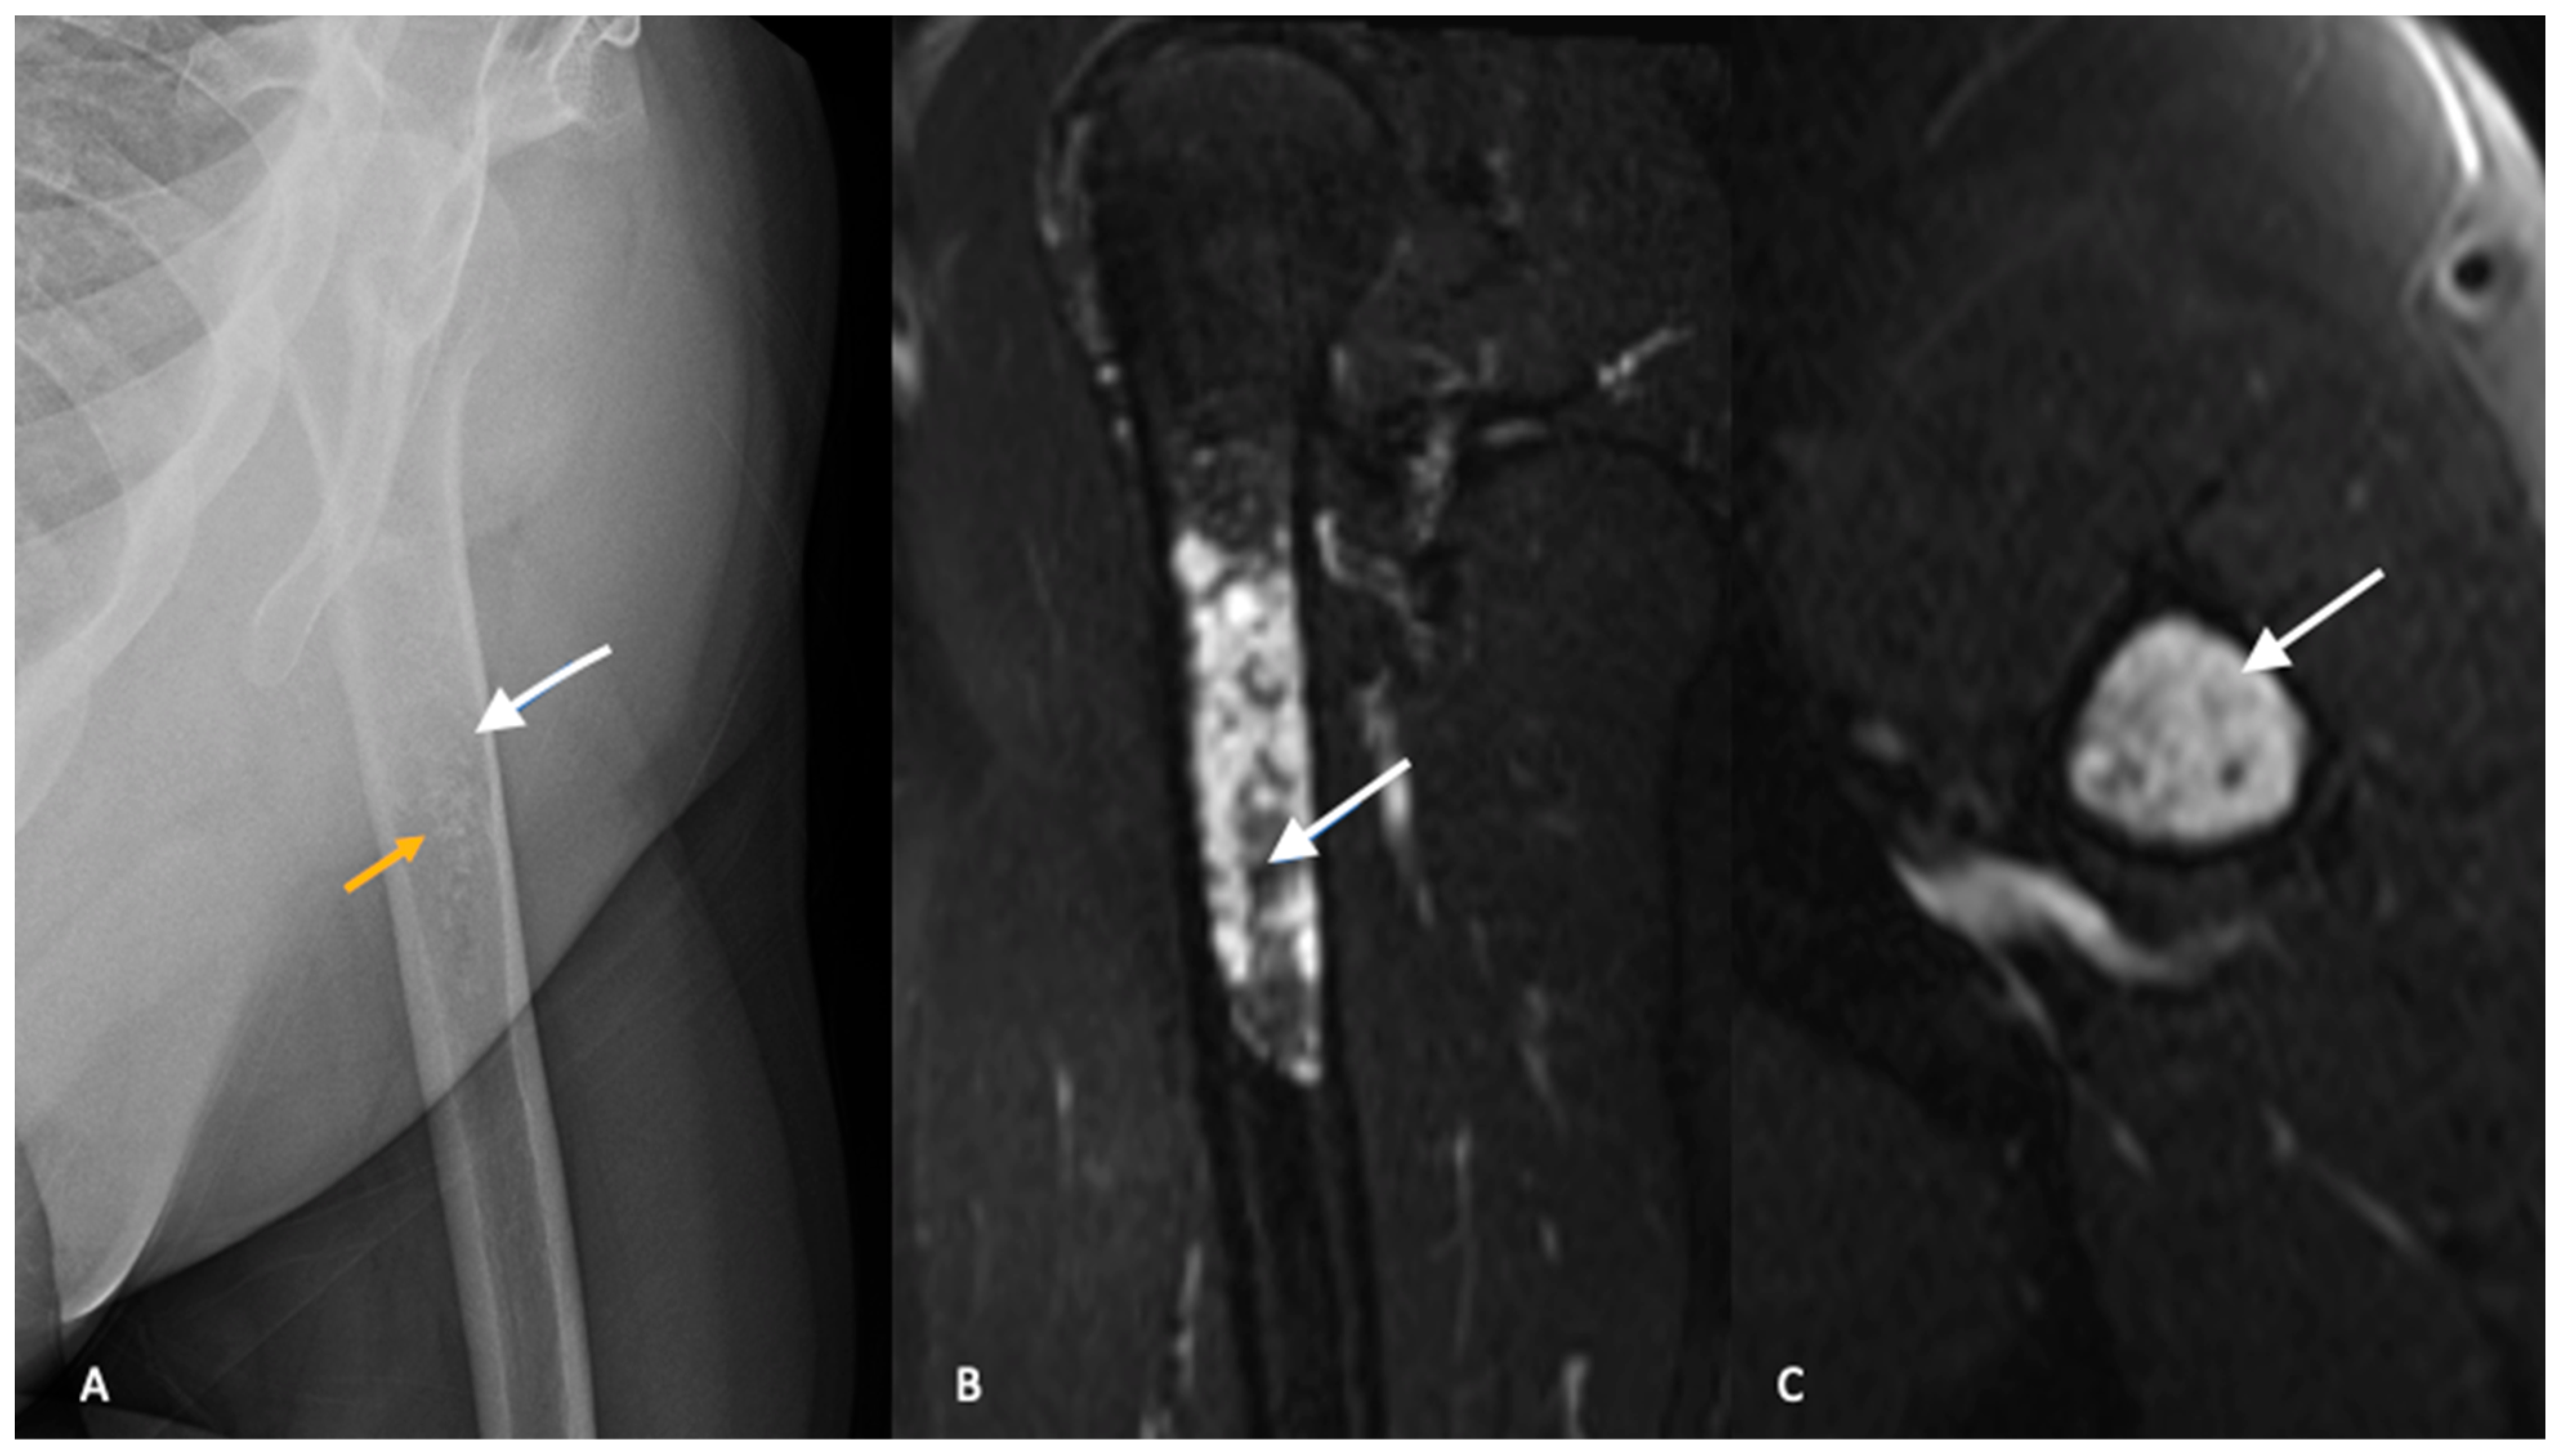

from www.cureus.com

A ct scan of the chest should be performed in all patients to detect the presence of pulmonary metastases. Extraskeletal cases are extremely rare. Chondrosarcoma is the most common primary bone cancer in adulthood, and. Chondrosarcoma is a rare cancer that most often forms in the bone, but can also very rarely appear in the soft tissue. Chondrosarcoma is a rare type of bone cancer that develops in cartilage cells. Chondrosarcomas are a group of rare bone cancer tumors that begin in your cartilage. Your doctor may ask about your signs. Tests and procedures used to diagnose chondrosarcoma include: Here, sarcoma medical oncologist anthony. Chordoma arises from the persistent notochordal elements in the spine (sacrum 50%, mobile spine 20%) and in the skull base (30%).

of Iliac Bone Imaging Spectrum With Histopathological